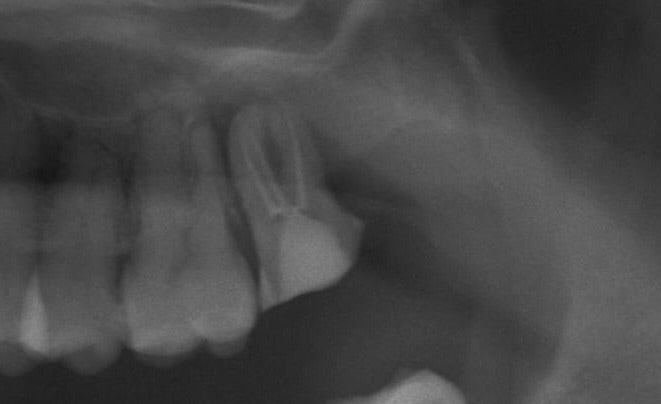

<抜歯後>

しっかりとカウンセリングを行い不安を軽減してから無痛リラクゼーション抜歯により施術を行いました。